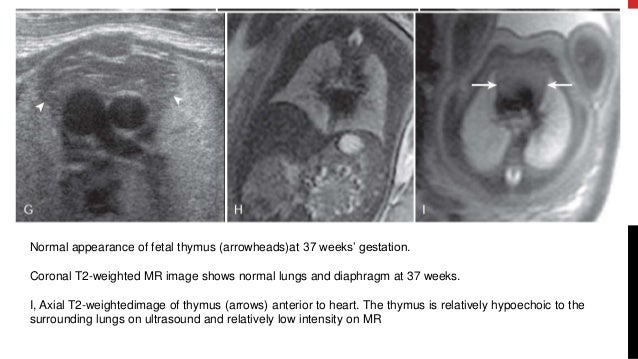

Fetal Anomaly Scan Chest Git Gut